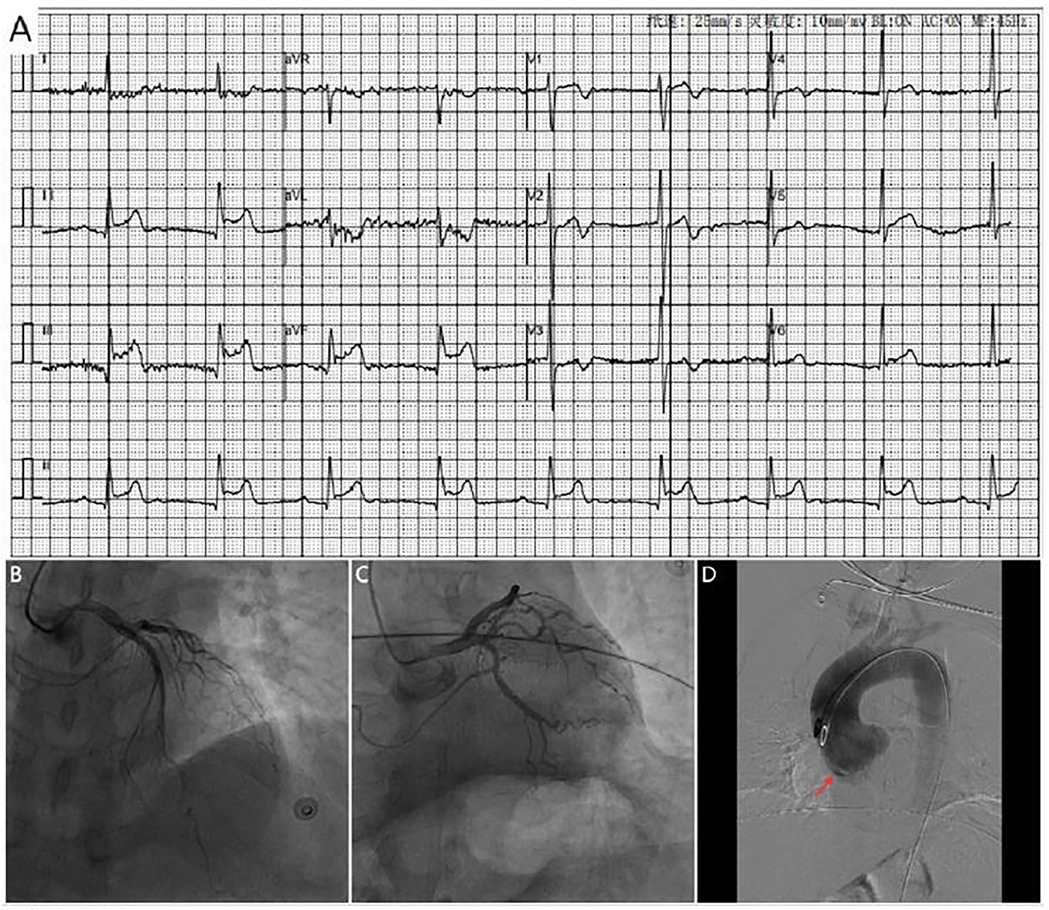

A 71-year-old woman with hypertension presented with chest tightness and diaphoresis. ECG revealed inferior STEMI and sinus bradycardia (Figure 3A). CAG demonstrated complete proximal RCA occlusion (Figures 3B–D; Supplementary Video 3) without visible intraluminal plaque on IVUS, but persistent extrinsic compression (Figures 3F–I; Supplementary Video 4). A drug-eluting stent (DES) was deployed at the ostium of the RCA with restored flow (Figure 3E). IVUS confirmed complete ostial coverage of the RCA and good stent apposition (Supplementary Video 6). CTA demonstrated mild aortic root dilation and right SOV dissection (Figures 4A–C; Supplementary Video 7). TTE demonstrated an intramural hematoma originating at the ostium of the RCA within the right coronary sinus, with partial extension into the proximal RCA (Figure 4D). The patient declined surgery and was managed conservatively. She remained stable with no recurrent symptoms during follow-up.

Figure 3

(A) ECG shows marked ST_segement elevation in leads II, III and avF, along with sinus bradycardia. Coronary angiography shows no significant stenosis in the left coronary artery (B,C) and complete proximal RCA occlusion (D), A DES (yellow arrow) placement at the RCA ostium with restored antegrade flow (E). (F–I) IVUS shows extravascular dissection (red arrow) and hematoma compressing the RCA (area marked with red asterisks).